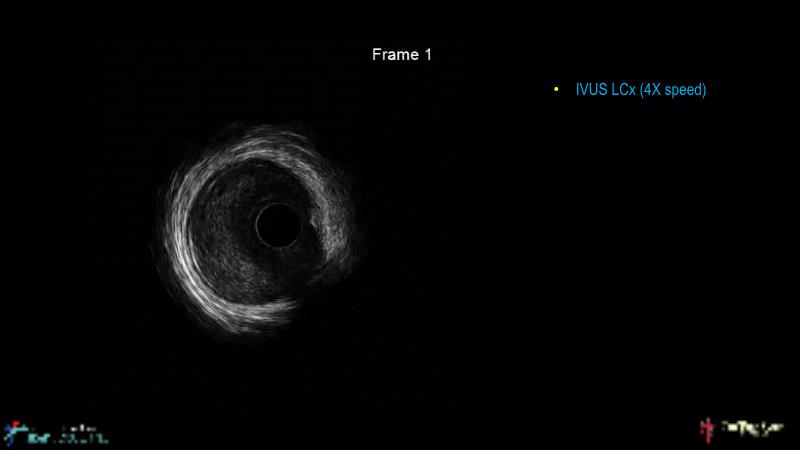

This session is recommended for you if you are seeking insights into the advantages of using IVUS imaging over visual assessment for better outcomes in left main bifurcation procedures. Discuss with experts the benefits of using RotaCUT in lesion preparation for left main bifurcation and explore the impact of high radial strength stents on the procedure's success.

• To understand why the use of IVUS imaging is different from seeing with experienced eyes to achieve improved left main bifurcation outcome